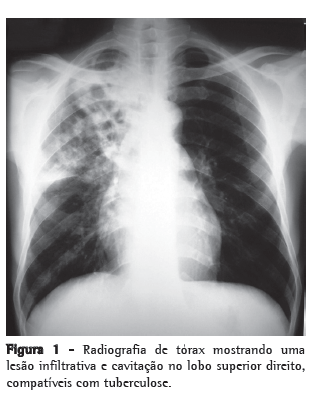

Estava acianótico e apresentava respiração normal. A radiografia de tórax (Figura 1) revelou uma consolidação infiltrativa nos lobos médios e superiores do pulmão direito, sugestivo de cavitação. A baciloscopia mostrou um grande número de BAAR, sugestivo de tuberculose, que foi confirmada pela cultura para Mycobacterium tuberculosis. Foi internado na enfermaria de isolamento e começou um regime antituberculose quádruplo com isoniazida, rifampicina, etambutol e pirazinamida. A sorologia para HIV-1 e HIV-2 foi negativa. A cultura de urina e múltiplas hemoculturas foram negativas durante a internação.